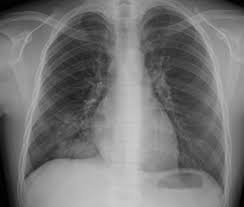

- 흉부 X-ray: 기관지 주위 침윤, 폐렴 소견